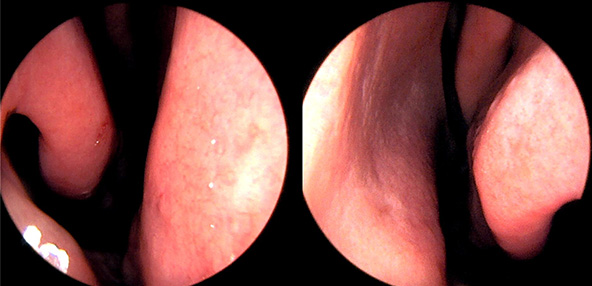

본 사진은 의료기관에서 진료를 본 환자이고, 전후 사진 인물이 동일인이며,동일조건에서 촬영이 되었습니다.